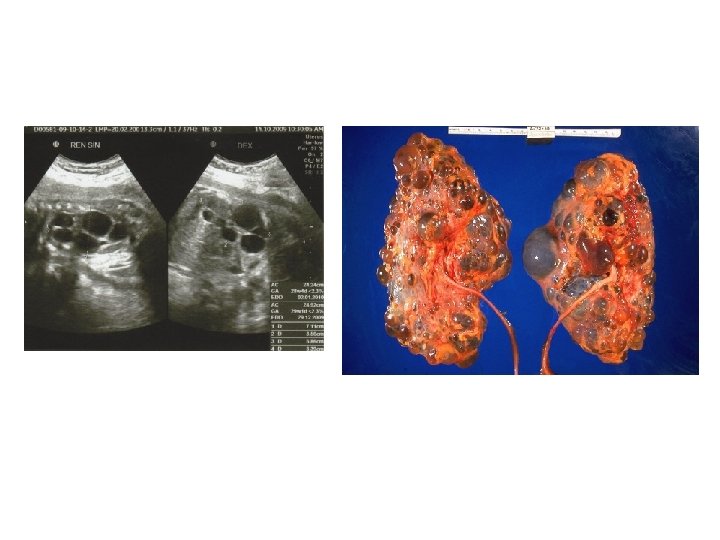

Kidneys malformations 4. Kidney displasia - Presence of embryonal structures is characteristic, which may come from vascular, nephroblastic or uretheral primordium. - The organs have different sizes, which depends on the presence of cysts. - It includes: multi-cyst displasia, oligomeganephronia (nephrone hypoplasia as well as decrease in the number and overgrowth of nephrones)

Kidneys malformations 6. Inborn hydronephrosis - Widening of the renal pelvis and calyces caused by difficulties in urine drain - Belongs to the most commonly diagnosed malformations of urinary tract - May be caused by: posterior urethral valve, urethral obstruction, vesicoureteric reflux, neuropathic bladder